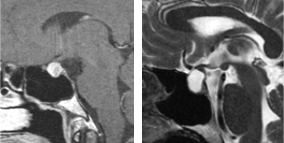

(下垂体腺腫の経年変化;矢印(↓)は視神経です。2010年の所見と比べ2016年では視神経が腫瘍によって下から圧迫され伸展しています。当初無症状だったため経過観察しておりましたが、視野障害が出現したため、初診診断後から10年目に手術しました。)